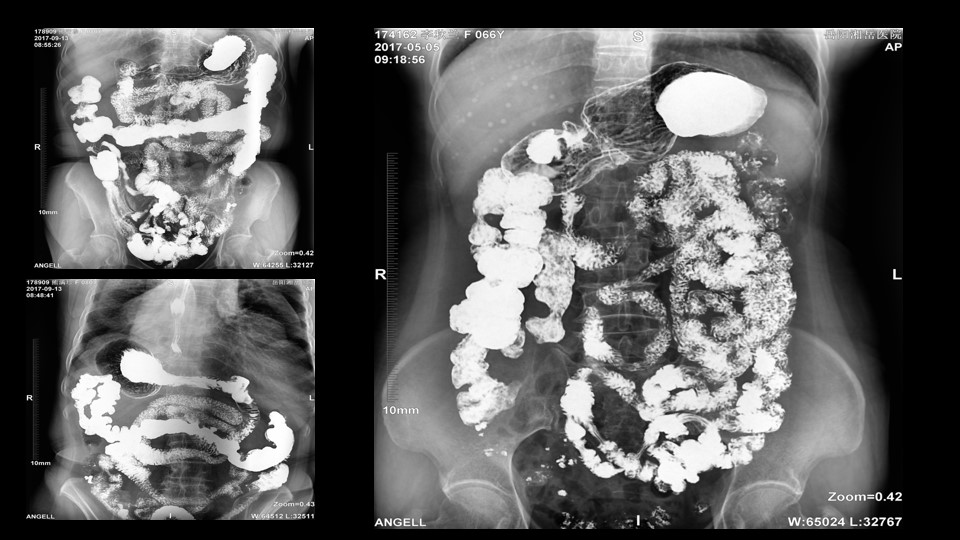

會議開始,岳陽市醫學會放射分會副主委、湘岳醫院放射科蔡雨主任,結合自身在放射影像的20多年經驗,為參會嘉賓分享了動態DR在消化道造影中的應用價值。作為動態DR用戶,蔡雨主任結合動態DR的實際拍片與操控經驗,分享了動態DR技術在相關群體疾病檢查上的獨到優勢和人文關懷。蔡雨主任說到:“隨著內鏡技術的發展以及CT、MR的發展,消化道造影在減少,但是這并不意味著消化道造影的價值在下降。以老年人為例,很多老年群體都患有嚴重的心肺疾病、或者消化道畸形,很多老年人本身就有糖尿病、高血壓等等綜合疾病,傳統內鏡的檢查對于這類群體來說是一件難以忍受的痛苦,而動態DR的多項創新技術讓這類群體的消化系統疾病篩查變得更為人性和精準。任何一個好的消化道造影,一定是患者、診斷醫生、臨床醫生三方滿意的結果。安健科技動態DR技術利用900萬像素高清拍片、大幅面透視、高清點片、視頻保存與回放等核心功能,完全滿足臨床對消化道氣鋇雙重造影檢查的需要。圖像質量全面超越以往模擬胃腸機、影增數字胃腸機”。蔡雨主任全面演示了動態DR在食道造影、上消化道造影、小腸雙對比造影、結腸氣鋇雙對比造影中的應用,通過動態DR可以清晰獲得臨床診斷和評估的圖像依據。

蔡雨主任使用動態造影圖像示例

湖南影像學委員、婁底市放射學會副主任委員、婁底市中心醫院放射科劉海潮副主任,則結合動態DR設備的全身拼接應用,分享了動態DR在骨科中的多項應用價值。劉海潮主任認為:由于常規DR的技術限制,長期以來放射科應用傳統拍片并不能有效解決重疊部位的清晰顯影,容易造成漏診誤診,并且受制于成像視野的大小,不能有效顯示脊柱四肢全長的整體結構及病變。而動態DR的17*17英寸大視野成像,配合900多萬的高清像素及可視化的操作,較好地彌補了傳統拍片的不足,而且初步實現了普放向精準診斷方向的轉變劉主任分享了動態DR在全脊柱攝影、全脊柱拼接、脊柱畸形,全下肢X線攝影、全下肢拼接、關節置換中的多項應用,通過站立負重位,快速、便捷攝取 2~3 張原始圖像。在相鄰兩幅原始圖像的重疊部分,對重疊圖像的特征點迅速匹配,進行智能無縫融合處理,將數張有重疊部分的圖像拼成一幅大型的無縫高分辨率圖像。劉海潮主任評價:動態DR通過強大的圖像后處理技術,比如邊緣增強、灰階處理,以及對對比度和銳利度的可調節性,大大提高了拼接影像的質量

全身拼接應用示例